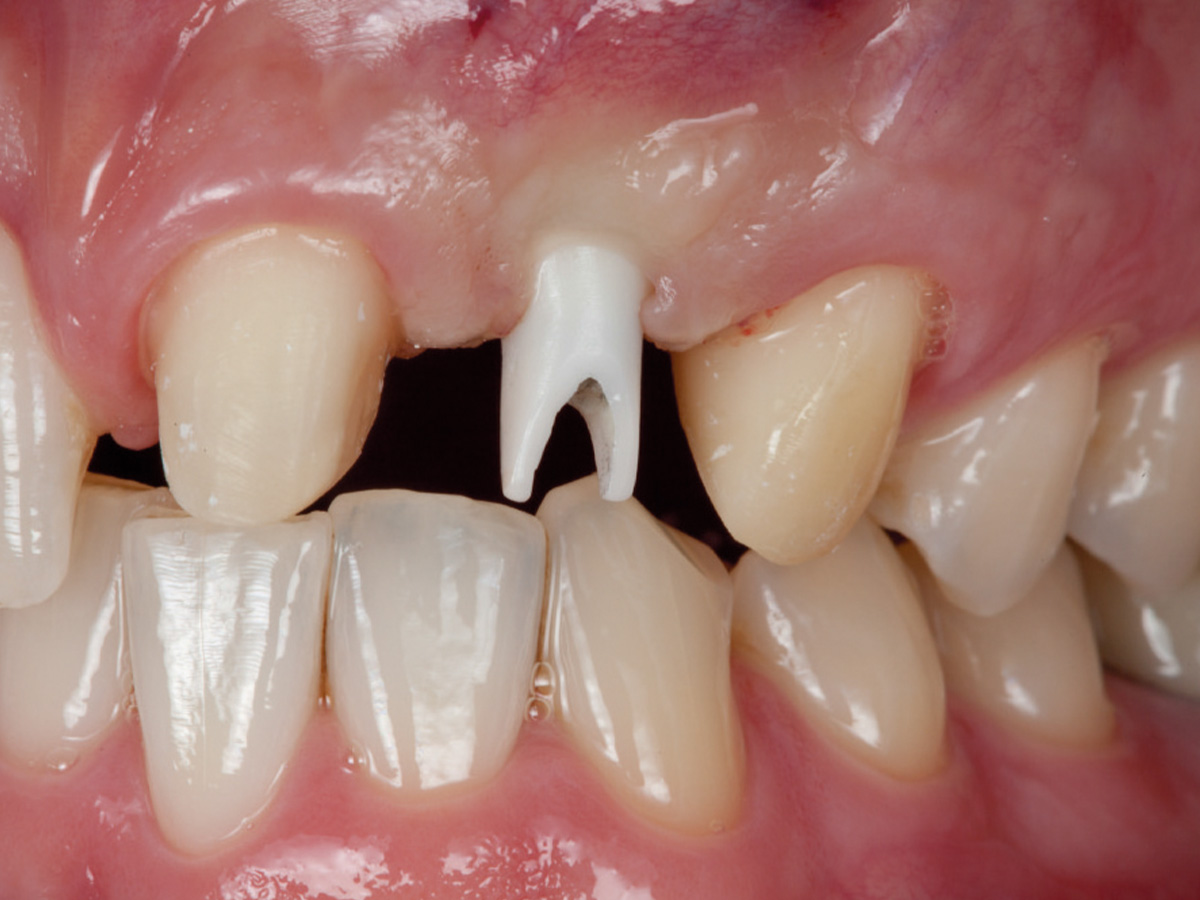

Abbildung 11

Ein Implantat mit 3,8 mm (Ø) konnte in seiner korrekten dreidimensionalen Position eingebracht werden.

Abbildung 12

Regenerierter Alveolarkamm vor der prothetischen Versorgung.